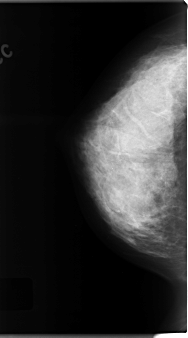

C_0120_1.RIGHT_CC

RIGHT_CC LINES 4720 PIXELS_PER_LINE 2632 BITS_PER_PIXEL 12 RESOLUTION 50 NON_OVERLAY